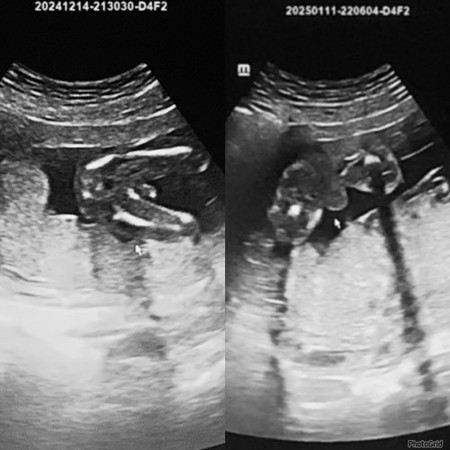

Doc kata baby boy tapi tk nampak bebird dia😂 agak2 ni betul ke baby boy ye ? tk sabar nk beli baju baby 🥰🥰 scan 17w & 21weeks

Sdah kangkang.. ada something kat tgh2.. kalau girl xda mcmtu.. dia rata je..

tp doc ckp masih tk nampak bebird dia 😂 yg nampak telur dia. Confius sy

batu dah terjojol bulat tu..myb kura2 nye pendek lg xnmpk😆

doc ckp tk nmpk pistol sis, 😅 nmpk telur dia je tu puas doc godek2